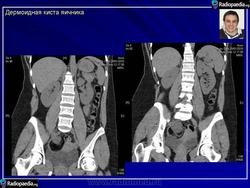

Зрелая тератома яичника.

Приложения:

101.pozhilye_kistoznoy_teratomy_yaichnika.jpg102.pozhilye_kistoznoy_teratomy_yaichnika.jpg103.pozhilye_kistoznoy_teratomy_yaichnika.jpg104.pozhilye_kistoznoy_teratomy_yaichnika.jpg